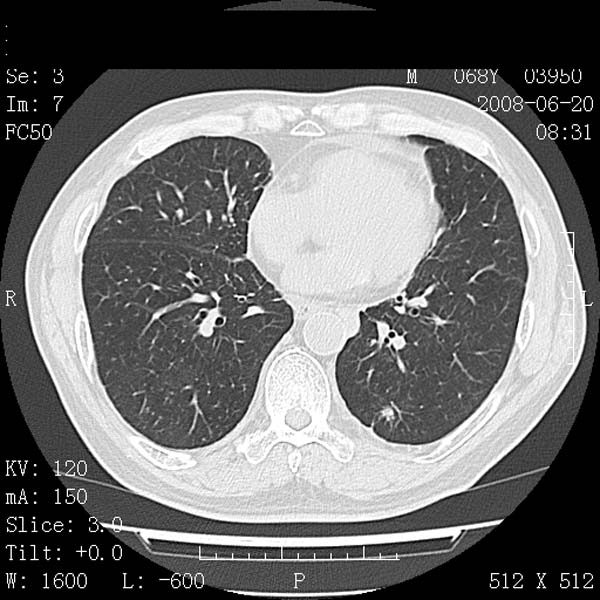

以下是引用守望可可西里在2008-6-24 1:11:00的发言:[br][br] 考虑为周围型肺癌:[br] 1.分叶结节,形态极不规则,蟹足样伸展的恶性浸润特征比较明确。[br] 2.磨玻璃影中由多个更高密度小结节聚集呈梅花瓣样。[br] 3.局部胸膜凹陷征比较明确。[br][br] 另:纵隔胸膜明显增厚、粘连。

以下是引用zjzjr在2008-6-24 11:19:00的发言:[br]支持左下肺周围型肺癌伴右肺转移,纵隔淋巴结转移,心包积液.

以下是引用zhangling在2008-6-24 14:56:00的发言:[br]我们科室意见报告为[br][br]1考虑左下肺周围型肺癌[br]2右肺小结节考虑转移瘤,纵隔淋巴结转移[br]3心包积液. [br] 各位老师分析的相当好 谢意[br]